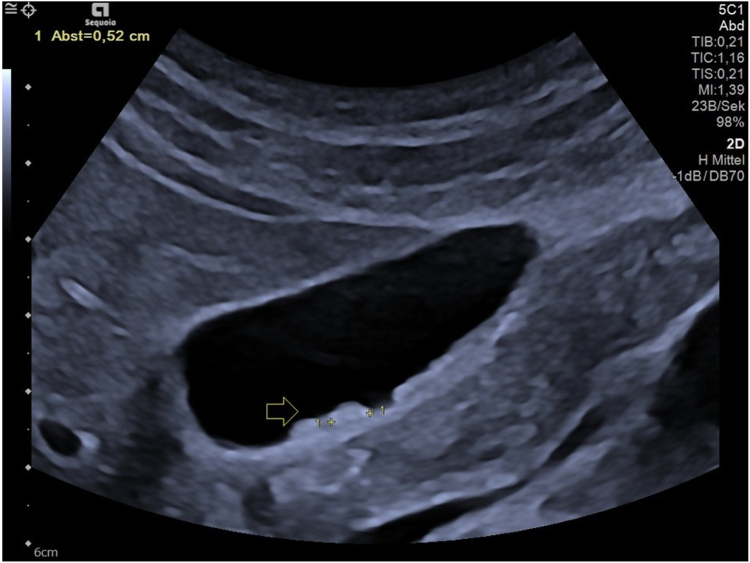

Case report: A 41-years-old male patient with sonographically confirmed, culture-negative endocarditis accompanied by repeated fever episodes received 4g ceftriaxone per day next to ampicillin and gentamicin as an element of his antibiotic therapy. At day 4 of treatment, signs of gall bladder sludge and biliary pseudolithiasis were first seen in sonography. At day 17, abdominal pain over 30 min and increased liver and pancreatic enzymes pointed towards temporal duct obstruction as a complication and ceftriaxone therapy had to be preterm cancelled. A sonographic work-up of the stepwise improvement of the sonographic findings after the end of the ceftriaxone therapy is provided, a reemergence of endocarditis was not observed.